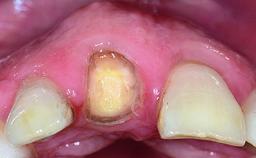

A 15-year-old male patient was referred to us by his pediatric dentist in June 2004 for evaluation of treatment options for his failing tooth 21. The patient had recently seen an endodontist for internal bleaching and been advised that there had been significant resorption and ankylosis. The patient’s mother was concerned because the tooth appeared shorter than the adjacent one. His past dental history was significant for trauma (September 2001), where the tooth had been avulsed and reimplanted. Teeth 11 and 21 had been endodontically treated.